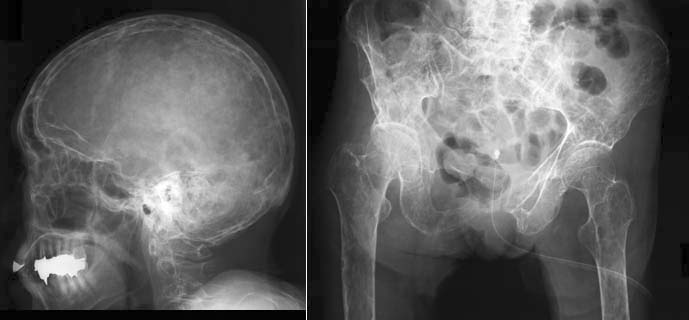

- 以下のような画像検査。

- X線

- 腫瘍による骨の穴